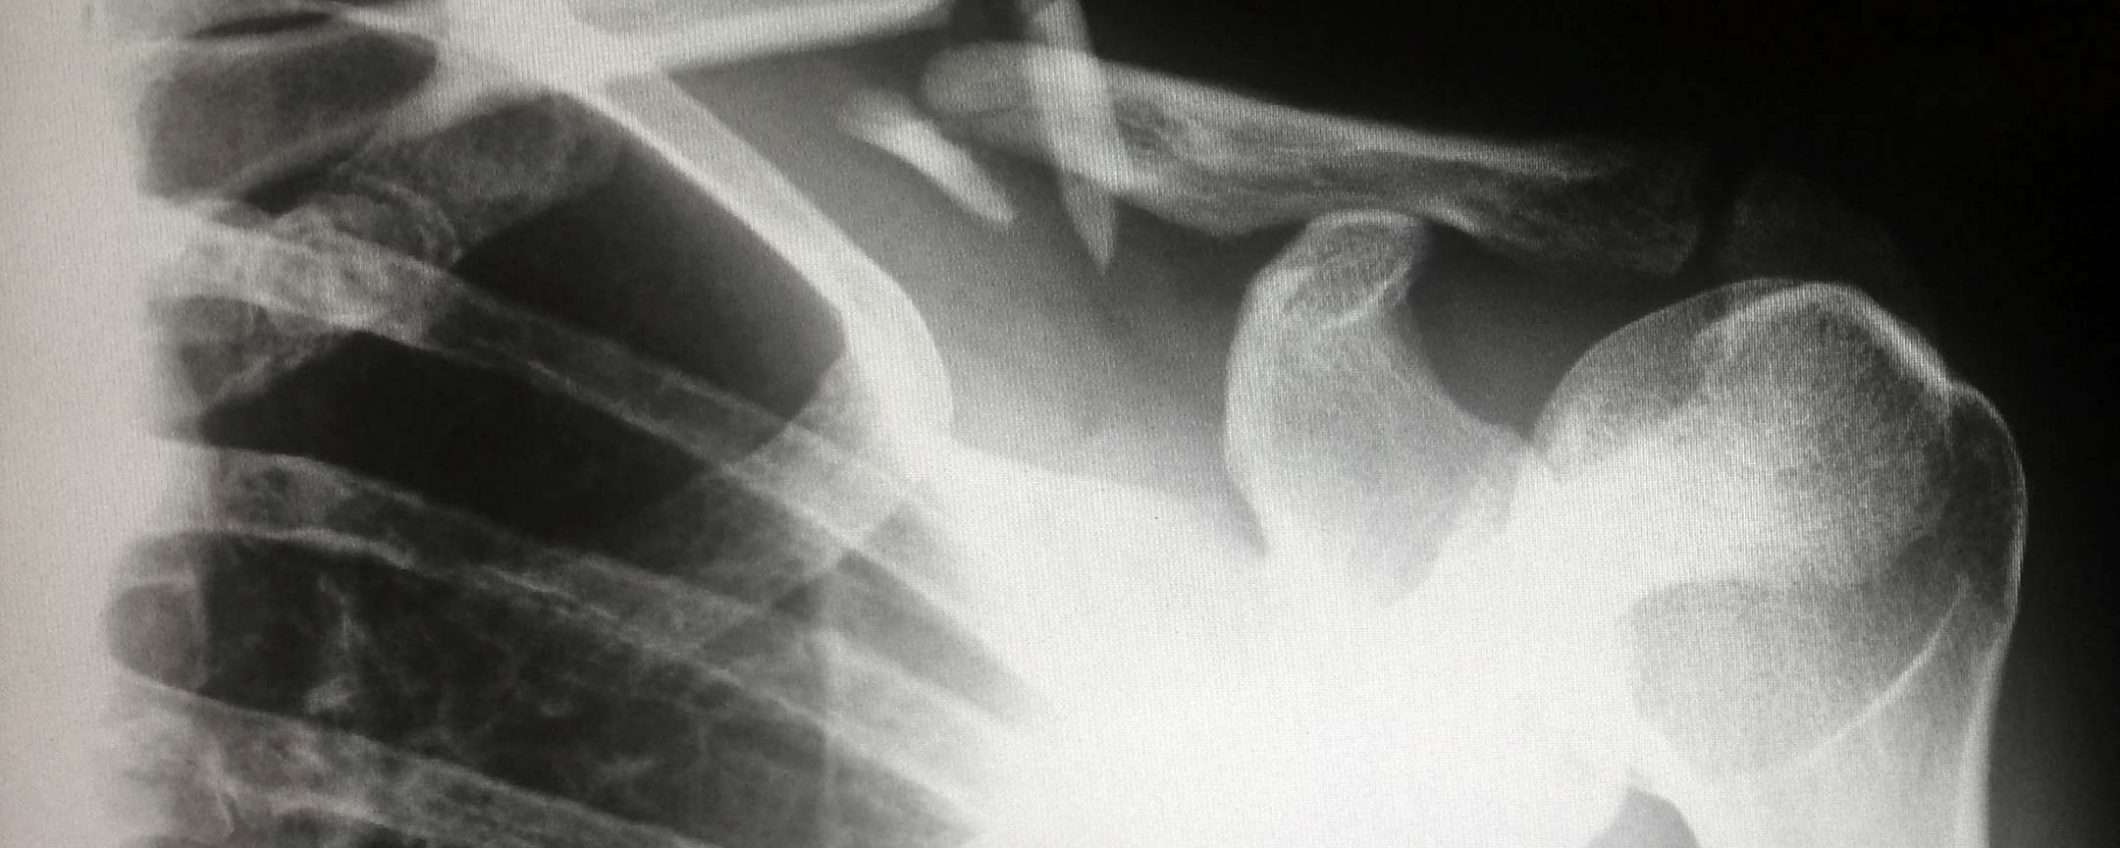

Un volume enorme di esiti di radiografie, TAC e altri esami medici liberamente accessibili da chiunque in possesso di una connessione Internet.

Da oltreoceano viene lanciato oggi un nuovo allarme: oltre un miliardo di referti sarebbero finiti online, scaricabili e consultabili liberamente da chiunque in possesso di una connessione Internet, ospitati all’interno di server collegati alla Rete senza alcun tipo di protezione. Un problema globale, non limitato a una particolare area geografica o a singoli territori stando a quanto riportano i ricercatori.

Focalizzando l’attenzione sugli USA, sono stati scoperti parecchi archivi in formato DICOM (Digital Imaging and COmmunications in Medicine) ospitati all’interno di sistemi PACS (Picture Archiving and Communicating System) da aprire e leggere mediante uno dei tanti software compatibili da scaricare gratuitamente. Il report pubblicato dal sito TechCrunch fa riferimento a un problema largamente diffuso, con gli avvisi forniti a medici e istituti largamente ignorati, nonostante le severe restrizioni previste dalla normativa HIPAA (Health Insurance Portability and Accountability Act) che prevede sanzioni elevate per coloro che non effettuano lo storage delle cartelle cliniche in modo rigoroso.